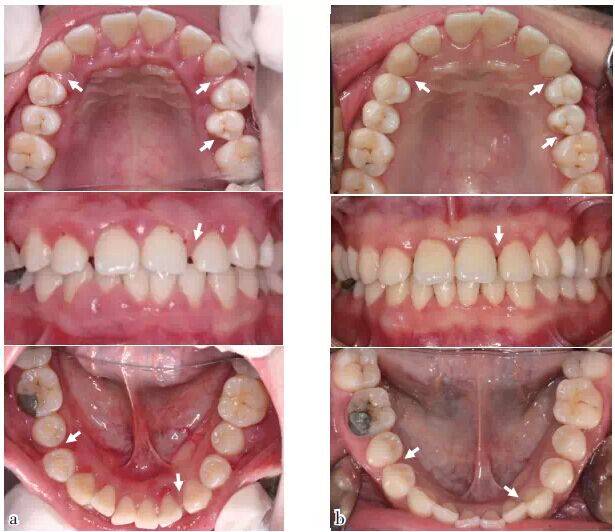

檢查 口外觀面部不對稱,張口時下頜左偏;牙齦紅腫出血,牙列欠整齊,牙間隙增大(圖1a),各項牙周臨床指標(biāo)見圖2a;CT體層片顯示牙槽骨廣泛吸收,嚴(yán)重者至根尖;右上頜竇炎癥(圖7a);CT圖像經(jīng)3D重建顯示牙尖交錯位異常。

圖1 口內(nèi)照:與初診相比,SRP及咬合干預(yù)后,牙齦炎癥減輕,25排列整齊,多處牙間隙變小或關(guān)閉(箭頭),(a)2011/12初診,(b)2014/11評估

在該病例中,患者面部不對稱、張口偏斜均是咀嚼肌作用的表現(xiàn),反映了咬合系統(tǒng)的不協(xié)調(diào)。由此產(chǎn)生的咬合創(chuàng)傷促使牙齒松動、牙間隙增大、牙槽骨重度吸收,并進(jìn)而導(dǎo)致牙源性上頜竇炎。

在對該病例行SRP治療的基礎(chǔ)上,針對病因進(jìn)行了咬合干預(yù)治療。通過上述治療,該患者最終未行拔牙、牙髓聯(lián)合治療和手術(shù)治療,原病變較嚴(yán)重的患牙亦得以保存;其次,咬合不協(xié)調(diào)得到改善,牙松動度明顯減小,且因牙槽骨骨量明顯增加,牙源性感染被阻斷,上頜竇炎得以減輕;最后,由于神經(jīng)-肌肉作用趨于平衡,牙列較治療前排列更整齊,牙間隙減小。